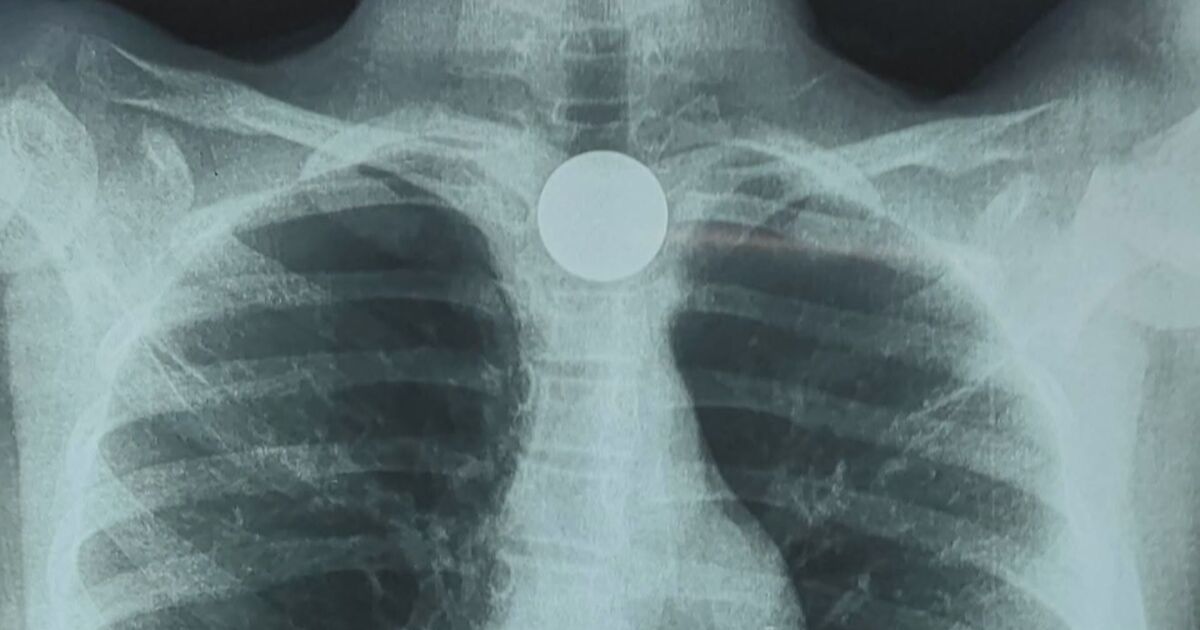

9-годишно момиче погълна голяма монета, която се заклещи в хранопровода ѝ. Това е четвърти подобен случай с деца през тази година във Фернандо де ла Мора, Парагвай.

Там лекарите извършили езофагоскопия, за да извадят монетата безопасно.

„Вчера пристъпихме към изваждане на монетата, която се беше заклещила в хранопровода. Тя не причиняваше дискомфорт при преглъщане, само малко слюноотделяне“, обясни д-р Мориниго.